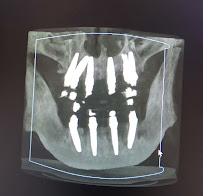

Dental Crepulja utilises modern diagnostic and imaging technology to underpin accurate treatment planning. The clinic is equipped with digital X-ray systems and CBCT (Cone Beam Computed Tomography), which produces high-resolution three-dimensional scans of the jaw, bone, and surrounding structures. CBCT imaging is particularly valuable for implant placement planning, as it allows the surgical team to assess bone volume, identify anatomical landmarks, and position implants with precision before any procedure begins.